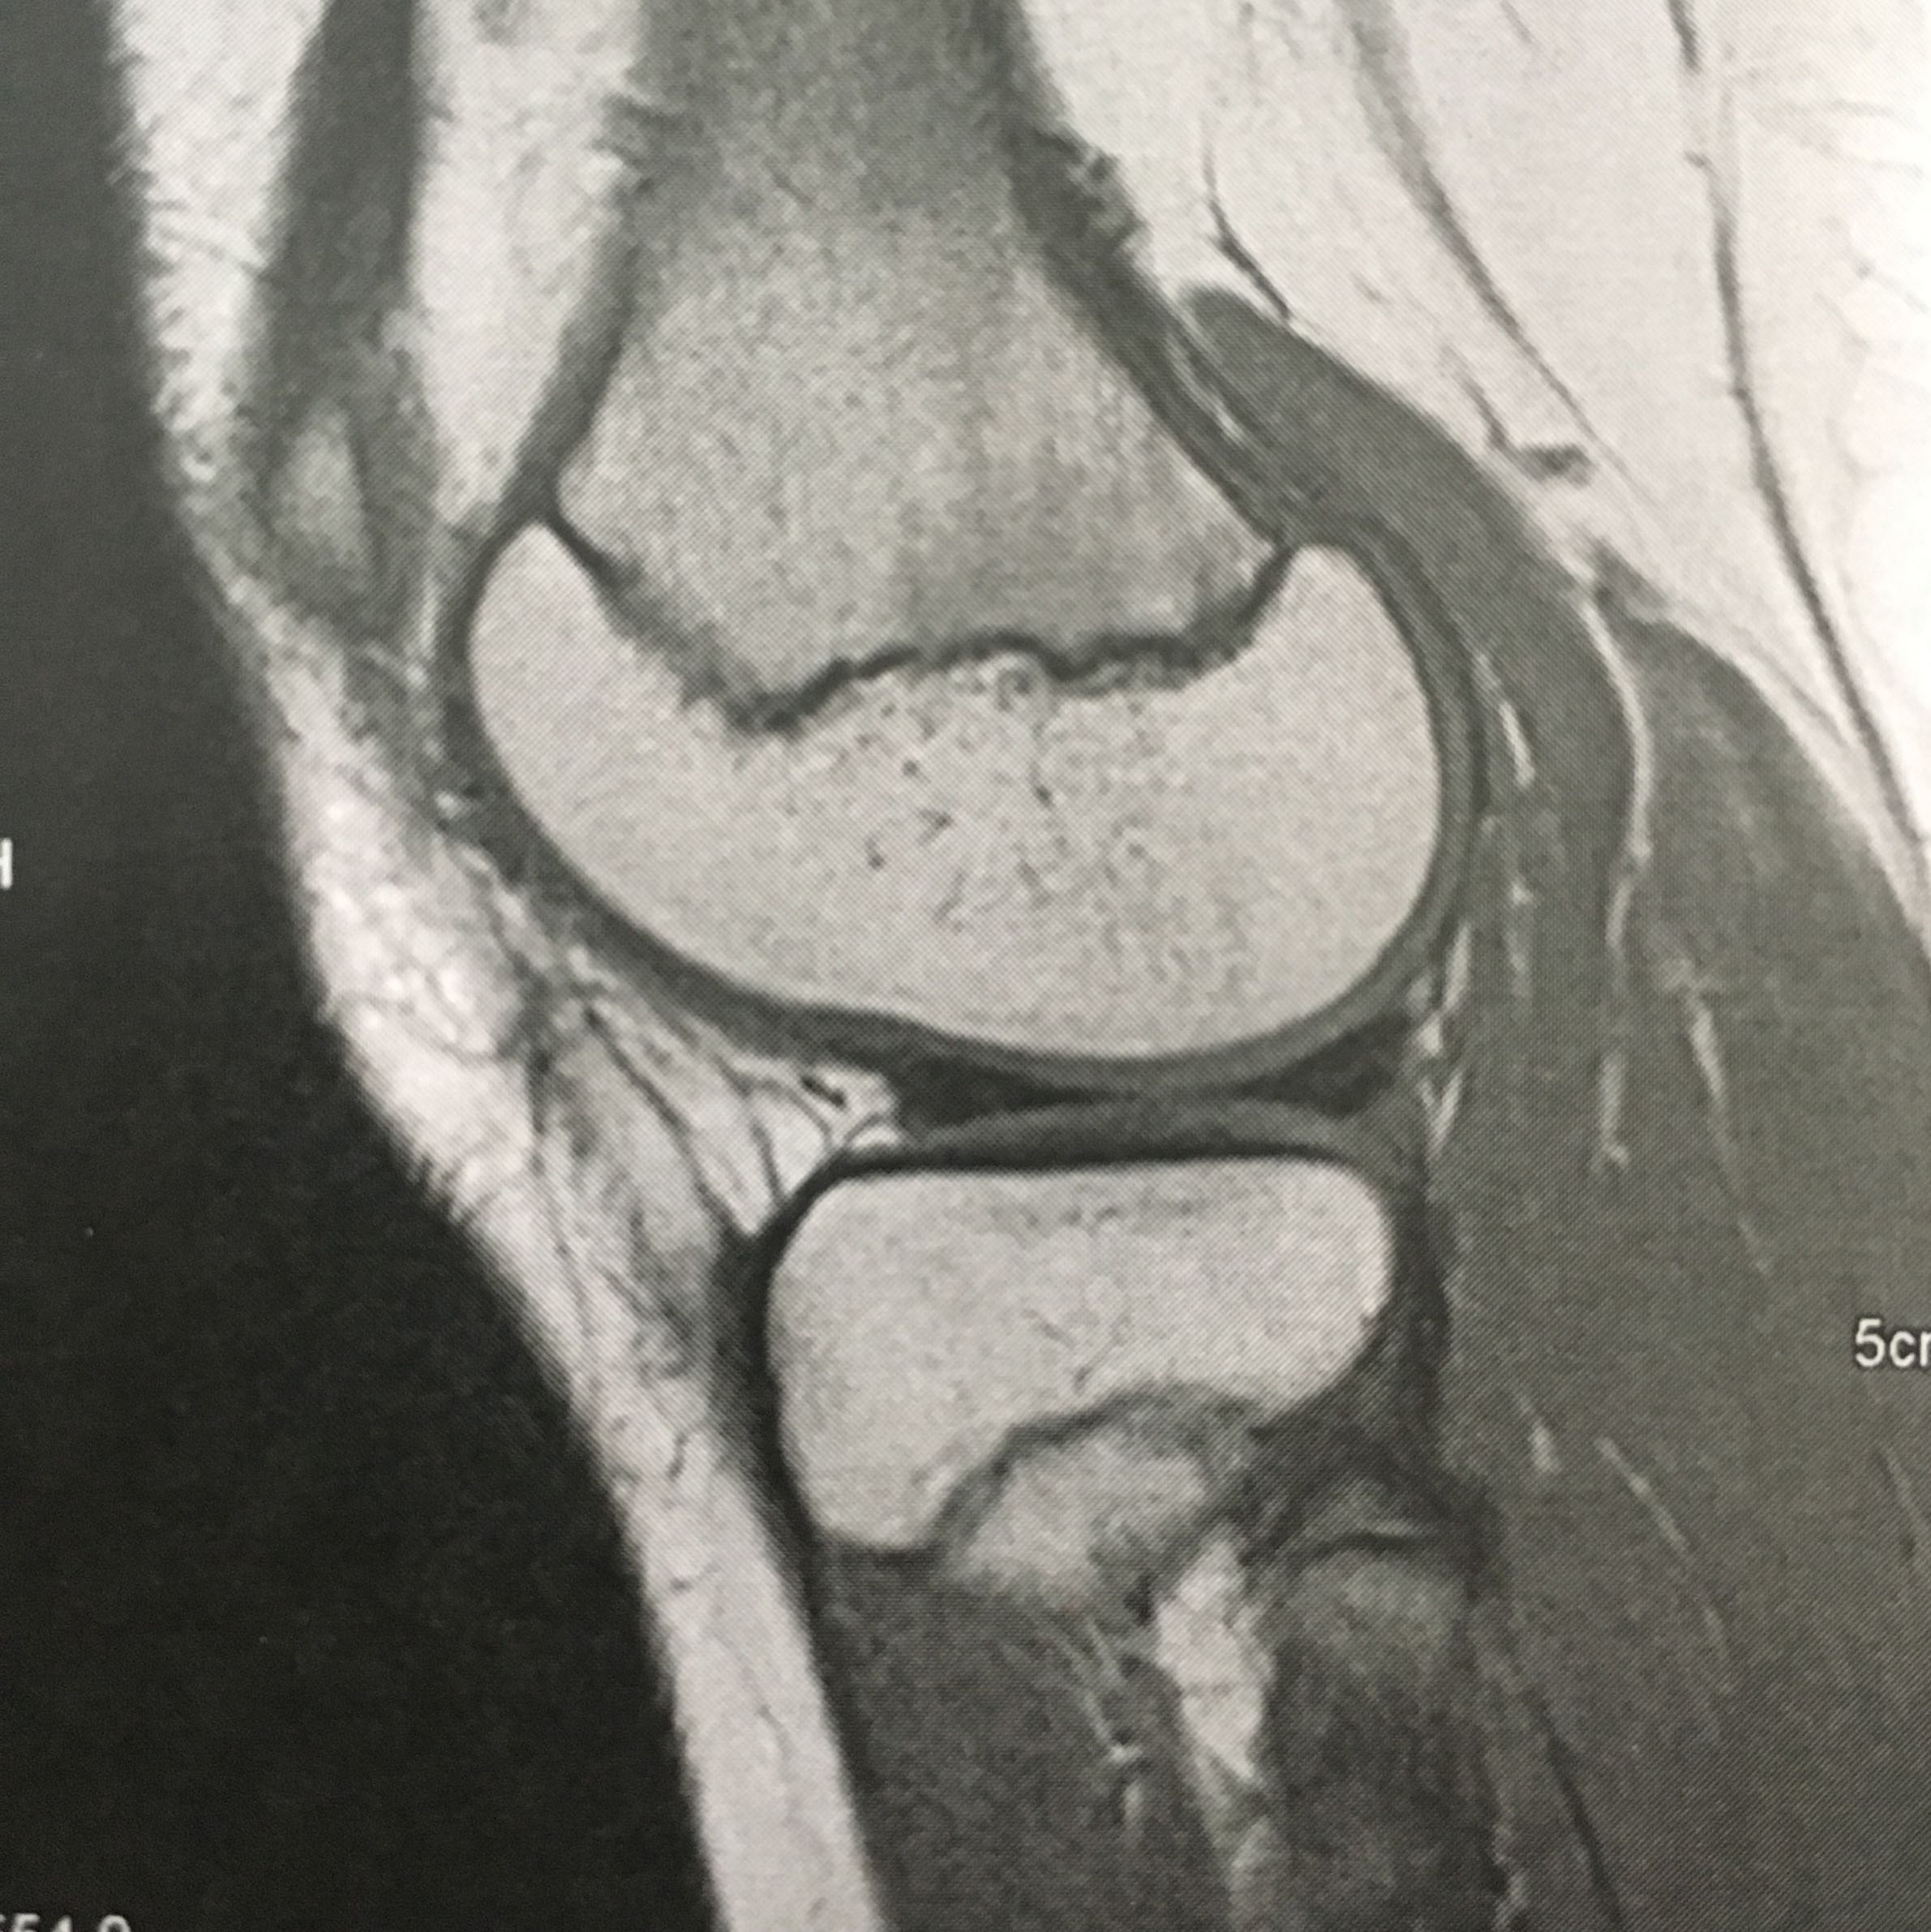

Ich habe hier ein paar Bilder, die ich euch zeigen möchte. Sie zeigen mögliche Probleme, die man haben könnte. Das erste Bild zeigt ein MRT des Knies. Auf dem Bild sieht man, dass die Kniescheibe leicht schief steht und die Bänder etwas verdreht sind. Das kann zu Schmerzen im Knie führen. Wenn ihr ähnliche Schmerzen habt, solltet ihr zum Arzt gehen und ein MRT machen lassen.

MRT des Knies